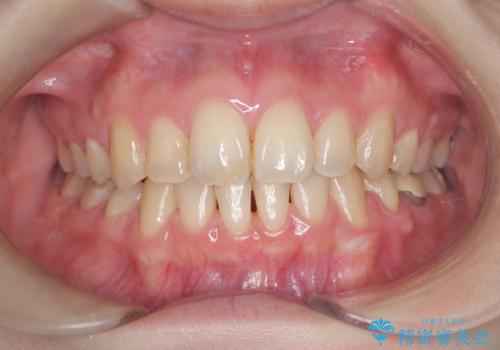

[マルチブラケットで後方移動] ワイヤー矯正で行う噛み合わせの改善